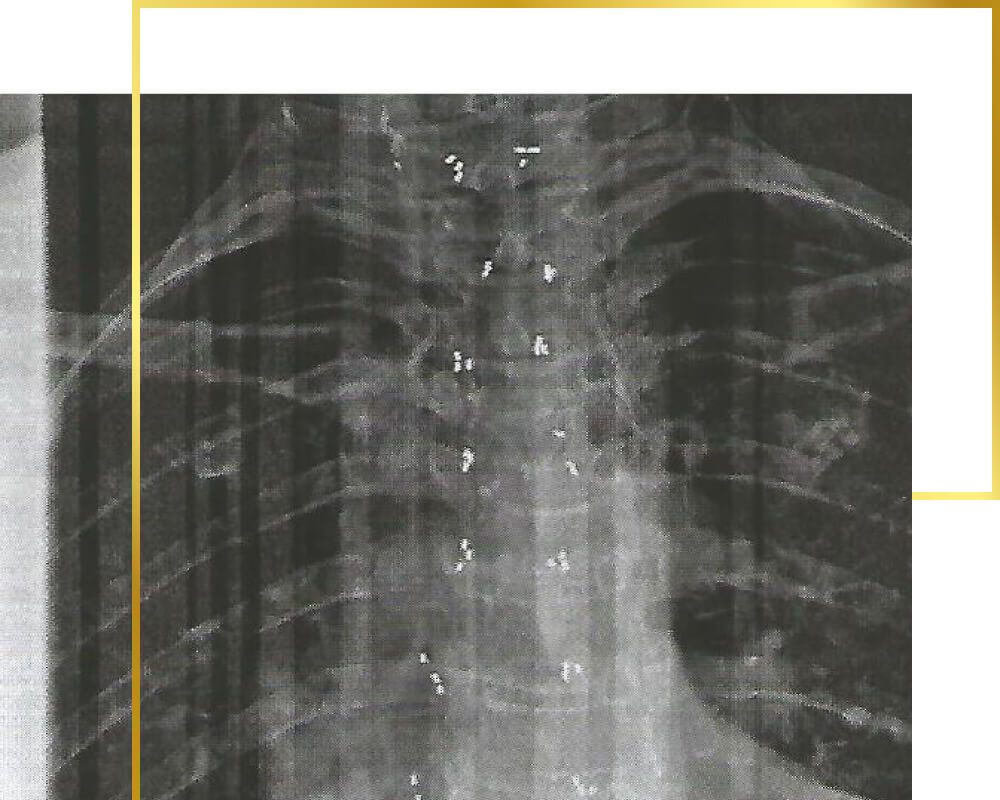

Back (cervical, thoracic and lumbar spine)

Just about everyone suffers from back pain in the course of their lives, often it is short-lived and is the result of incorrect movements or an unfavourable sleeping position. However, chronic painful changes can also occur in the cervical, thoracic and lumbar regions, which can lead to permanent back problems, migraines and other accompanying symptoms.

Back pain is also a great burden for sufferers during the day - the pain often comes in waves or short, stabbing pains rob them of their breath. The gold implants act directly on the joint and ensure that movements can be carried out fluidly and the body can regain strength through a restful night.